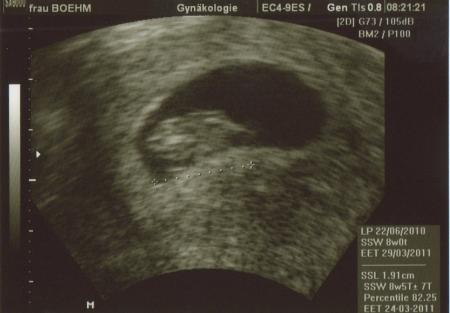

US Bilder 6+0 und 8+0

es ist schon krass Größe vervierfacht in 14 Tagen ich seh schon wieder ein 4,5 Kilo Kind auf mich zukommen *g